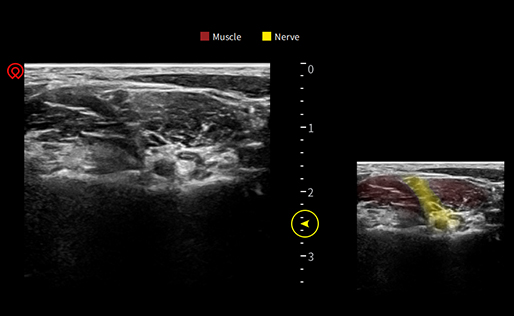

wiNerve

Reconocimiento de nervios con IA

Reconocimiento en tiempo real

Auto-evolución en la nube

Soporte para múltiples nervios